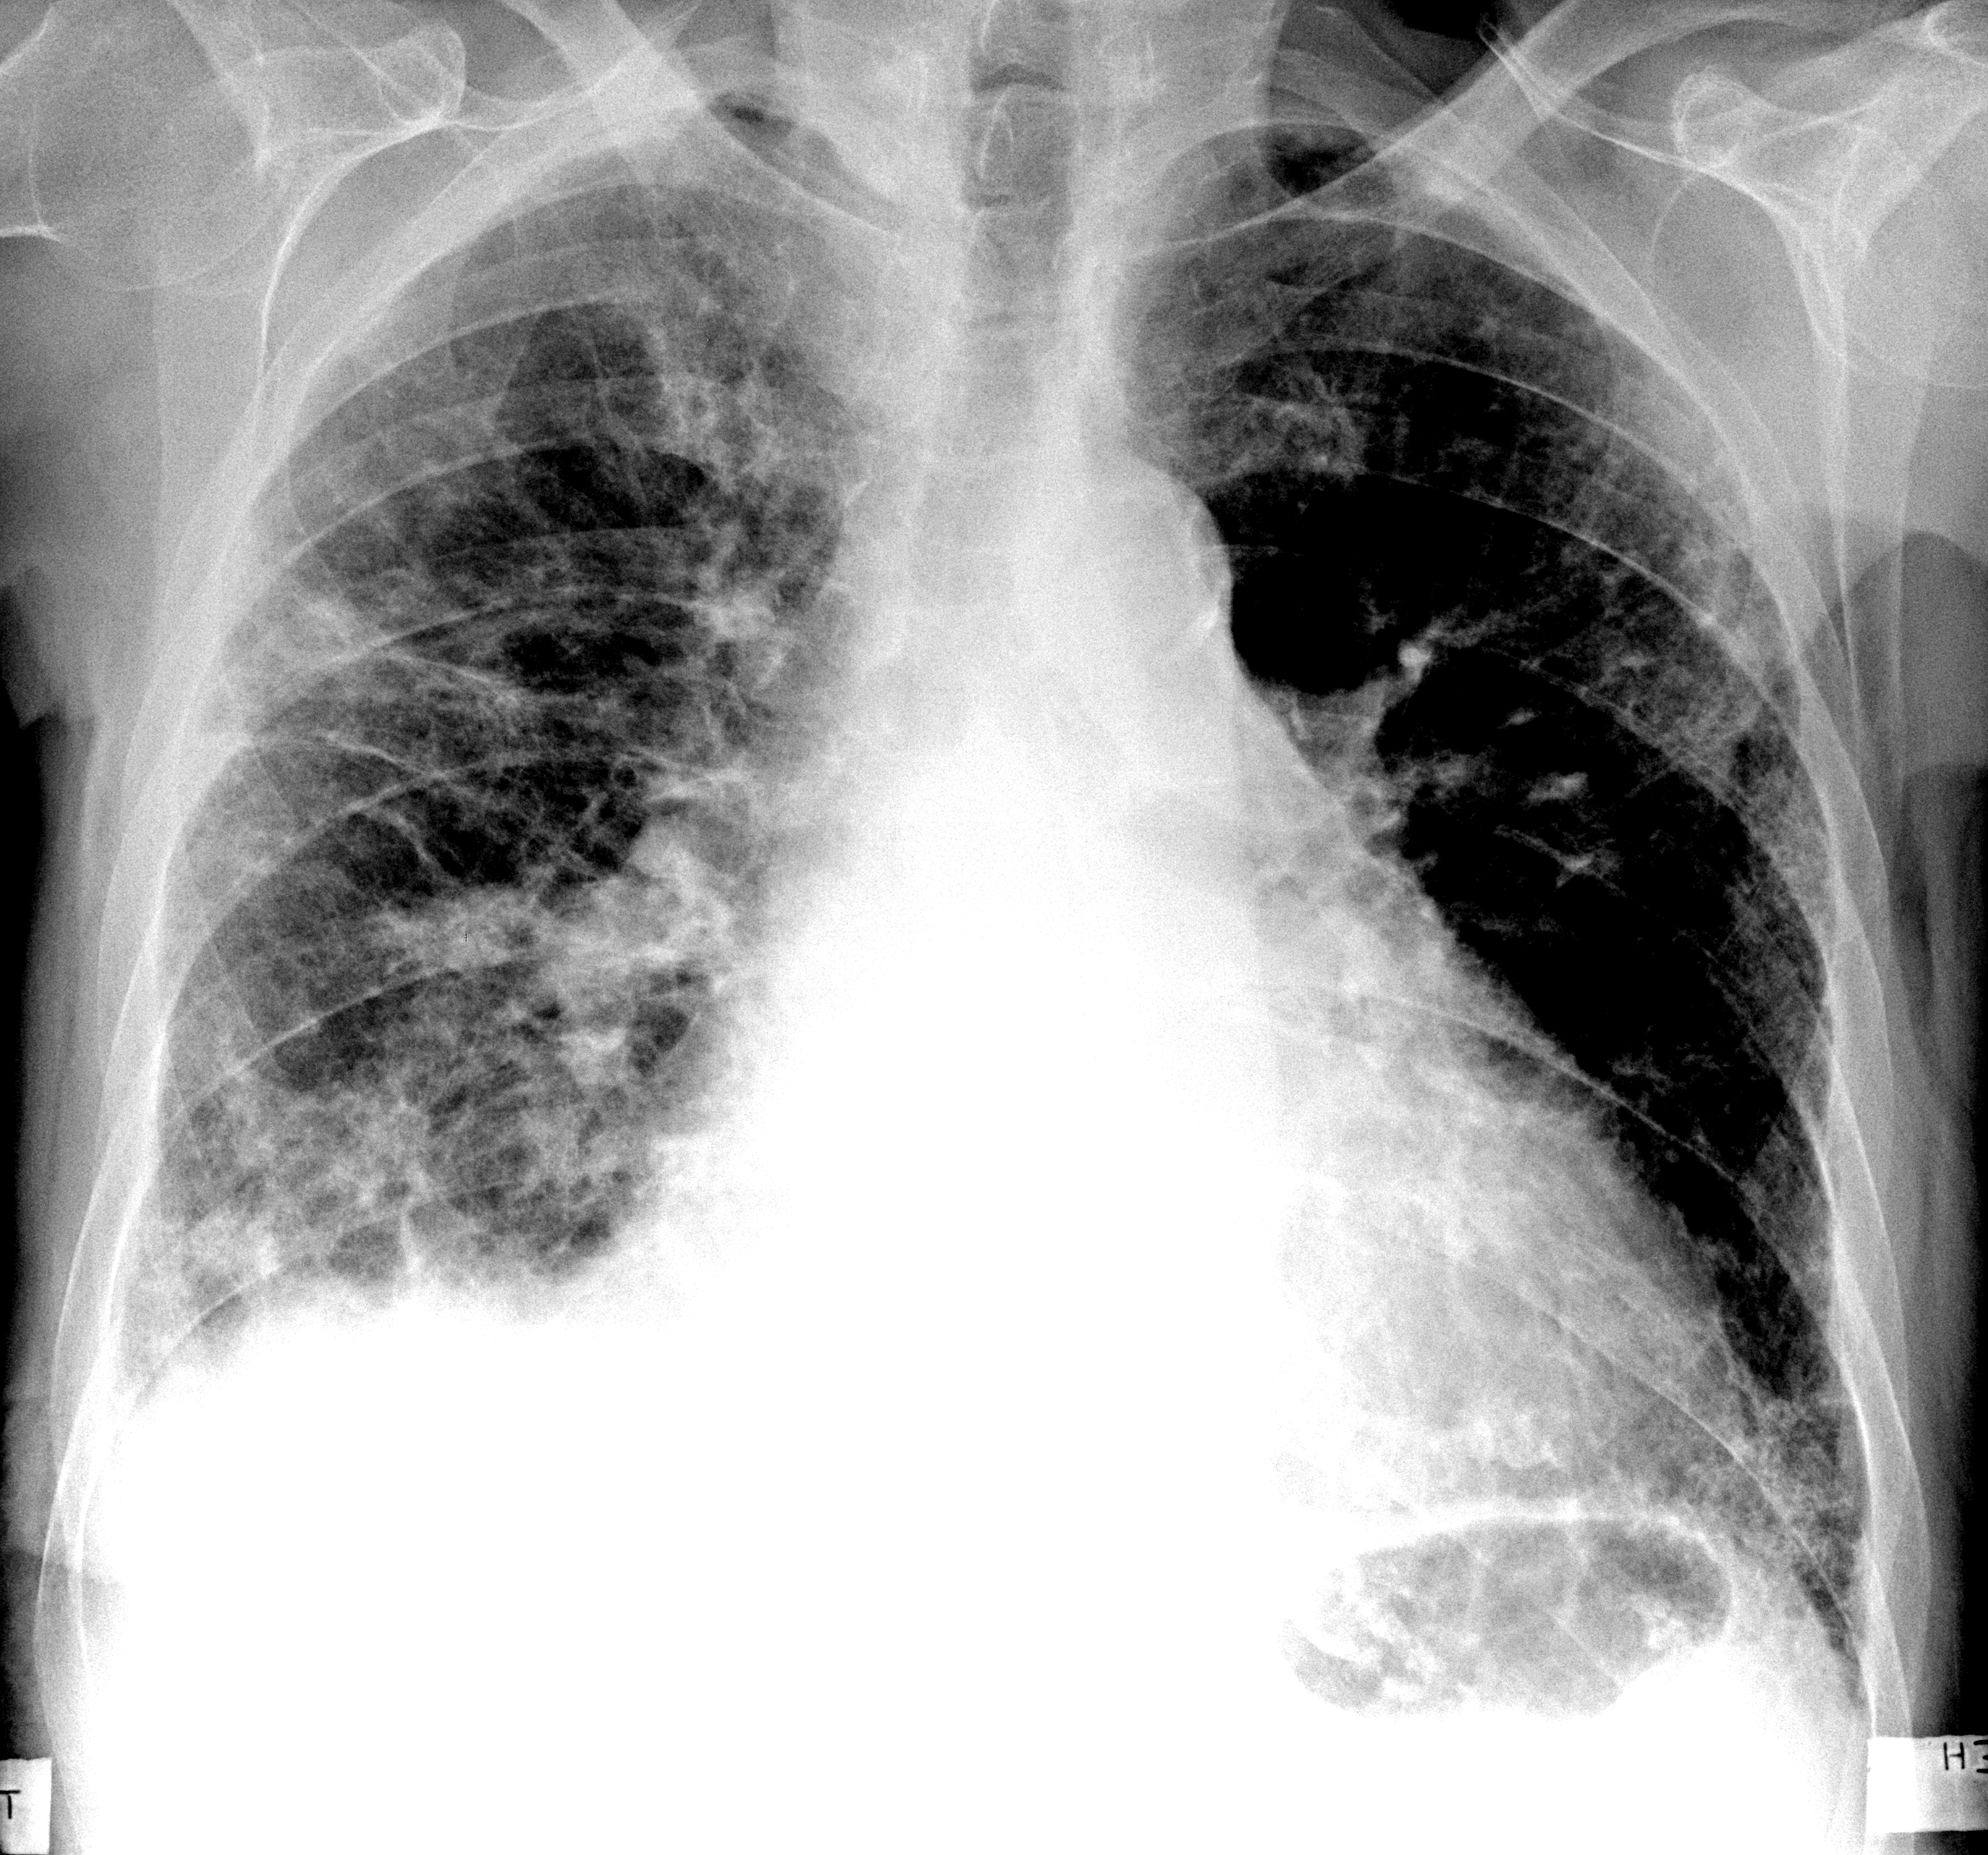

Рентгеновские снимки при врожденной эмфиземе легкого

Раздел: Визуальные уроки